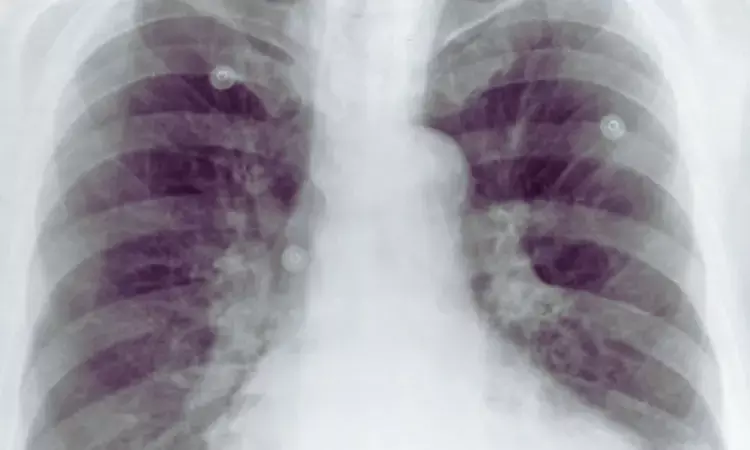

Aortic Calcification on Chest X-Ray Signals Poorer Survival After Minor Limb Amputation: Study

Finland: Aortic calcifications (ACs) visible on routine chest radiographs may signal worse survival prospects for patients undergoing minor lower limb amputation, a study published in JVS: Vascular Insights has shown.

- A total of 62.1% of patients had detectable aortic calcifications on preoperative chest x-ray.

- Severe AC was present in 21.9% of patients.

- In unadjusted analyses, severe AC was associated with more than a threefold increased risk of poorer overall survival (HR 3.165).

- Severe AC was linked to nearly threefold higher risk of reduced amputation-free survival (HR 2.972).

- Severe AC was also associated with a significantly increased risk of impaired leg salvage (HR 2.495).

- After adjustment for other variables, severe AC remained significantly associated with worse overall survival and amputation-free survival.

- The association between severe AC and leg salvage did not remain significant in multivariable analysis.

- The overall presence of ACs was associated with poorer overall survival (HR 1.669).

- The presence of ACs was also linked to reduced amputation-free survival (HR 1.587).